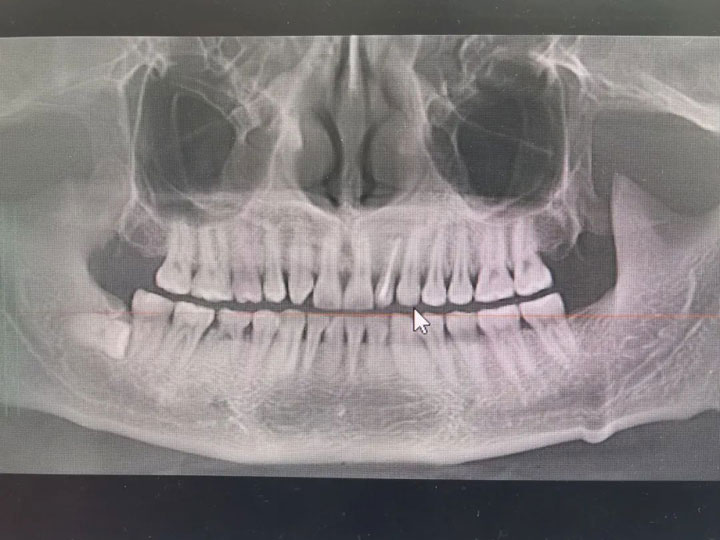

“医生,我的牙还有救吗?”面对马女士的询问,接诊医生孙翔仔细检查后,告诉她:“您的龋齿现在已经发展成为牙髓炎,要想彻底治愈牙疼,只有进行根管治疗才可以。”为了让马女士更好地了解什么是“根管治疗”,孙医生拿起桌上的模型,讲解了治疗的大致过程。

根管治疗术又称牙髓治疗,是治疗牙髓病及根尖周病的最有效的一种方法,也是目前保存患牙最好的治疗方法。通过清除根管内的炎症牙髓和坏死物质,进行适当消毒,严密充填根管,以防止发生根尖周病变或促进根尖周病变的愈合。

牙髓炎,牙髓坏死各种类型的根尖周炎基本适于作根管治疗,其中包括由于龋齿、隐裂、磨耗、穿髓等引起的牙髓炎及根尖周病变。

根管治疗的全过程一般包括牙体准备、开髓、确定根管位置、拔髓、确定工作长度、根管预备、根管消毒、根管充填、牙体修复。一般情况下,根管治疗需要就诊2~4次。